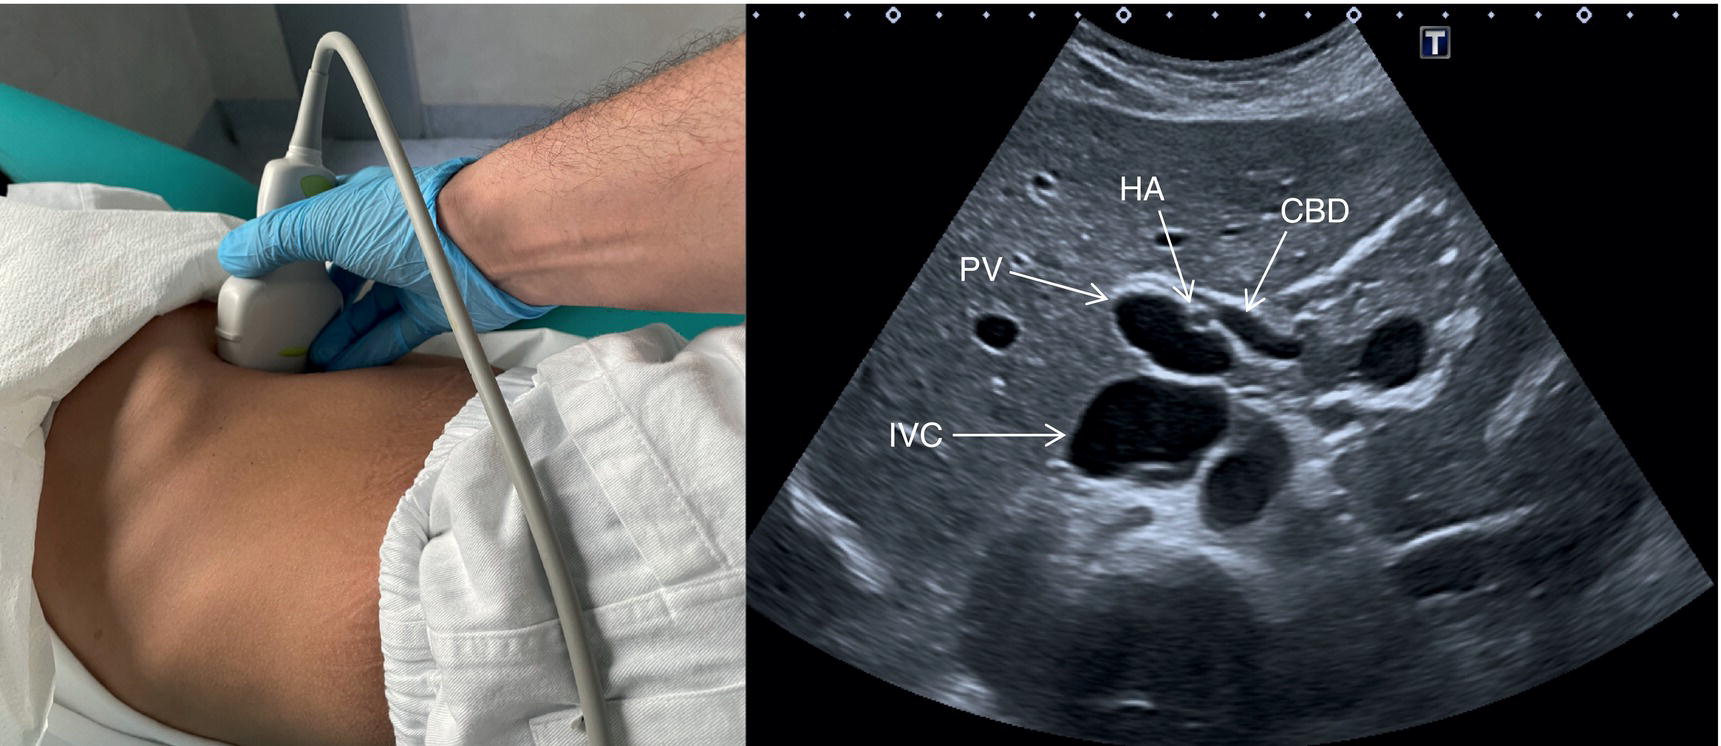

In normal physiological conditions, the CBD is the only biliary duct that can be clearly seen as a thin tubular structure with echogenic walls that in the majority of cases runs anteriorly and parallel to the PV at the level of the hepatic hilum (Figure 3.8). However, the anatomical relationship of the biliary ducts and the portal vessels may vary along their course, and usually the peripheral biliary ducts (which are only clearly visible when dilated or significantly thickened) run posteriorly to the PV (Figures 3.9 and 3.10).

Gallbladder and Common Bile Duct

The GB is assessed in the subcostal position, in two orthogonal planes, and also intercostally. As a first approach, place the transducer on the anterior abdominal wall along the mid‐clavicular line, adjusting its position until the GB is located. Ask the patient to take a deep breath to lower the diaphragm and push the liver downwards below the costal margin; this will facilitate GB visualisation. It is essential to image the GB in its entire long axis and to angle the transducer so that it is also imaged transversally. The longitudinal intercostal approach will complete the GB visualisation, also offering an alternative to a sometimes challenging subcostal view in case of bowel gas interposition (Figure 3.27) (Video 3.9). In other circumstances, especially in the presence of narrow intercostal spaces, an intercostal approach might not be ideal. The CBD is best visualised with the patient supine or slightly turned with the left side down. Start with the probe obliquely positioned in the epigastrium, in line with the anatomical plane of the CBD. Sweep subcostally and outwards until you see the image of the portal triad (Figure 3.28). This may require some fine adjustments of the probe position (Video 3.10). The CBD is usually measured longitudinally where the HA intersects the CBD and PV; nevertheless, if the CBD shows some size variations it should be measured at the level of its maximal calibre (Figure 3.29). As for the GB, there may be occasions, owing to bowel gas, in which the CBD is better visualised in the anterior intercostal plane (Figure 3.30). ![]()